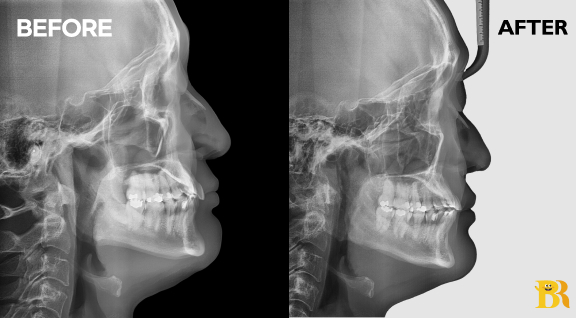

[전체적으로 불규칙한 치열 케이스] 발치하지 않고 교정치료를 진행 하여 치열 개선에 따라 옆모습도 좋아졌습니다